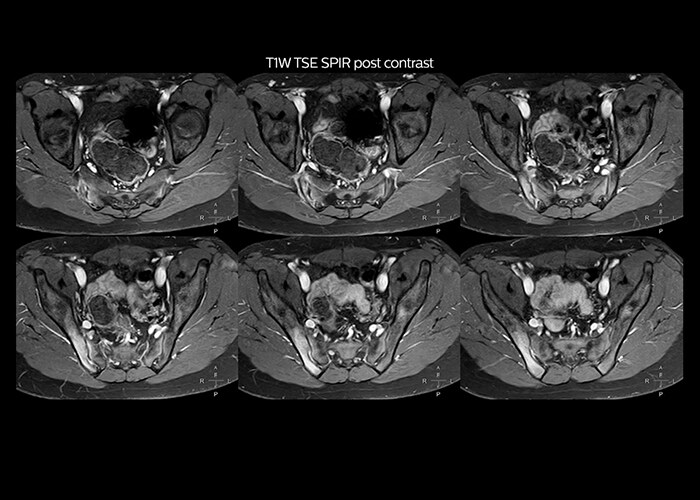

“On average, we scan about 80 patients per day, but on some days we scan well over 100 patients. The scanner is in use 7 days per week, operated 20 hours per day on week days and 8 hours per day in the weekend,” Mr. Tuna says.   “To avoid coil changes we plan examinations of similar anatomies back to back, such as head and spine. Multiva helps us here a lot because coils don’t need to be changed frequently. Moreover, thanks to parallel imaging technology and 16-channel HeadSpineTorso and 8-channel MSK coils we are able to achieve excellent image quality. In this way Multiva helped us to increase both image quality and productivity.”   “Neurological cases, such as brain and spine imaging, represent the largest share in our MR scanning, followed by musculoskeletal cases. In general, we use simple and basic imaging protocols. But occasionally, we use advanced techniques for problematic cases if necessary.

“Since we have Multiva, we have improved our workflow, because it has been so easy for our operators to learn and use Multiva. Our operators notice that the coils are lightweight and coils don’t need to be changed frequently. The user interface is easy to use. Features like this help us to scan a high number of patients. For instance, the musculoskeletal coils can be used interchangeably, and due to the user-friendly interface, the number of mistakes such as, for example, correct coil element selection has decreased significantly, because the system does it automatically by itself.”    “Most important, Multiva satisfies our clinical imaging needs very well,” says Mr. Tuna. “Many features of Multiva have become similar to the Ingenia system. Even in more complex imaging such as abdominal and cardiac, the image quality and performance of Multiva is better than we expected. General surgeons and physicians from our hospital’s internal medicine department prefer to refer to us because of this.”

“Overall, Multiva provides what we need in term of patient needs and even potential needs,” says Mr. Tuna. “It allows us to scan a high patient volume and image a large variety of anatomies and conditions.”   “Our goal is to achieve uncompromising quality based on universal standards, while solving clinically complex cases. Our Multiva scanner allows high productivity with fast imaging time, and allows us to make confident diagnoses in a broad range of cases.”   “It’s an excellent multi-purpose scanner that satisfies all our MR imaging requirements in the hospital,” he concludes.